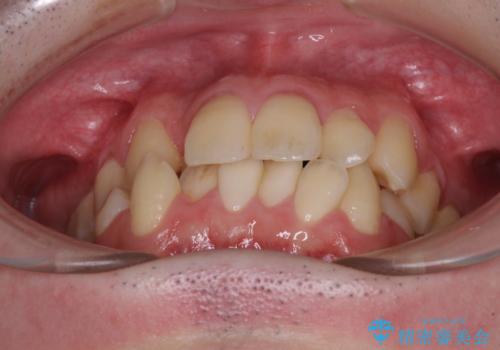

全顎的なクロスバイト 補助装置を用いてワイヤー矯正

- 八重歯や奥歯の噛みにくさを気にして来院された患者様です。

前歯のクロスバイトや八重歯の他に、左右最後臼歯のシザーズバイト(鋏状咬合)が認められました。

シザーズバイト改善のために補助装置を使用しながら、ワイヤー装置にて全体の歯列を整えることとしました。